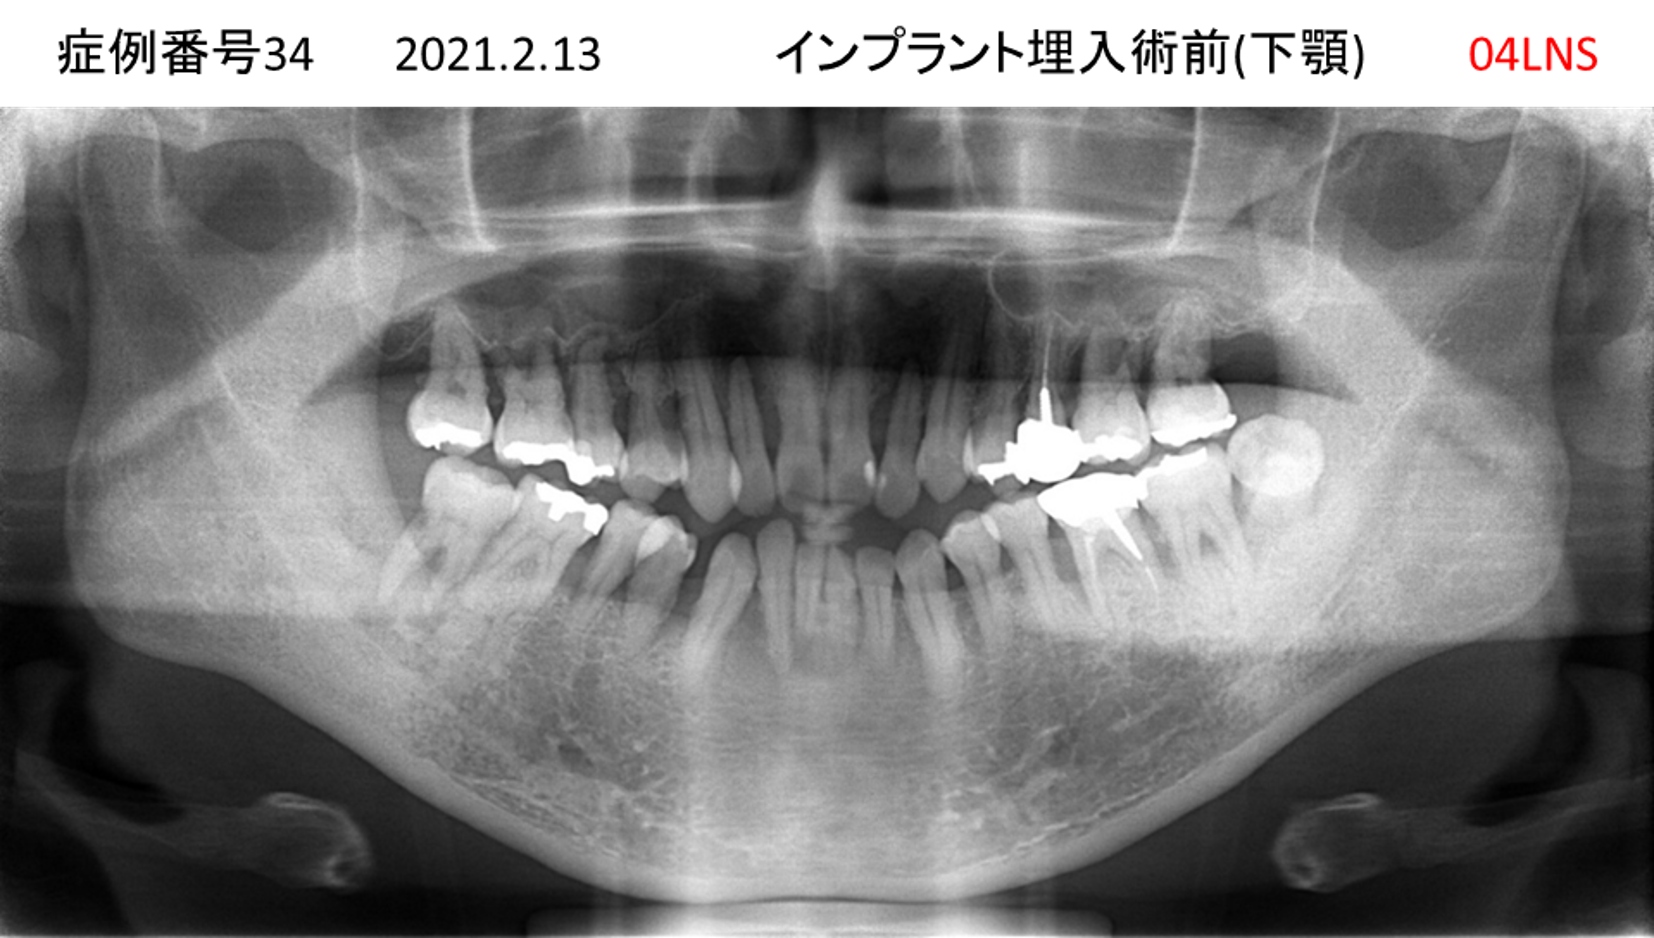

揺れている歯が多くて噛めない患者様のインプラント症例

| 治療名称 |

インプラント |

| 治療費用 |

440万円+税 |

| 治療期間 |

8か月 |

| 患者さんの症状(主訴) |

上の歯をはじめ、揺れている歯が多くて噛めない。食事ができない。 |

| 治療内容 |

サイナスリフト 抜歯即時インプラント |

| 治療結果 |

食事に困らない。見た目がとても良くなった。 |

| 治療の注意点(リスク/副作用) |

インプラントが壊れたら再治療が必要 |